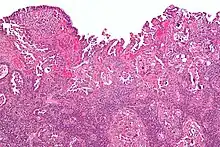

Histology H&E of uterine serous papillary carcinoma. H&E stain. |

Histopathologically, uterine serous carcinomas is typically characterized by (1) nipple-shaped structures (papillae) with fibrovascular cores (2) marked nuclear atypia (irregularities in the nuclear membrane, enlarged nuclear size), (3) psammoma bodies and (4) cilia.